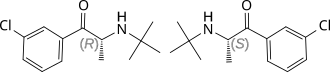

Chemistry

Bupropion is an aminoketone that belongs to the class of substituted cathinones and the more general class of substituted phenethylamines.[32][33] It is also known structurally as 3-chloro-N-tert-butyl-β-keto-α-methylphenethylamine, 3-chloro-N-tert-butyl-β-ketoamphetamine, or 3-chloro-N-tert-butylcathinone. The clinically used bupropion is racemic, which is a mixture of two enantiomers: S-bupropion and R-bupropion. Although the optical isomers of bupropion can be separated, they rapidly racemize under physiological conditions.[2][166]

Diagram showing the synthesis of bupropion from 3'-chloro-propiophenone. The α-carbon atom is an asymmetric one, tetraedrical HC*(CO)MeNH. So, bupropion is a chiral compound.